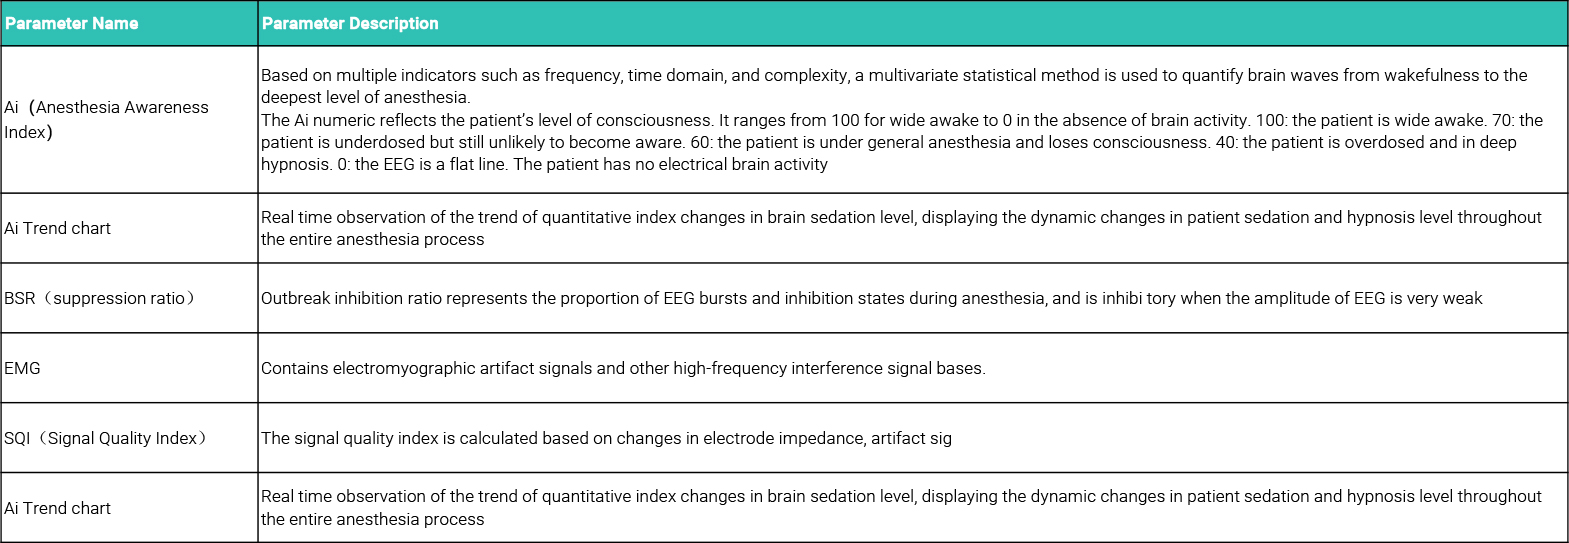

Basic principle of Ai anesthesia depth index: Ai anesthesia awareness index is based on multiple indicators such as frequency, double frequency, time domain and complexity.Multivariate statistical methods were used to quantify the brain waves from the awake to the deepest anesthetic state.

Basic principle of Ai anesthesia depth index: Ai anesthesia awareness index is based on multiple indicators such as frequency, double frequency, time domain and complexity.Multivariate statistical methods were used to quantify the brain waves from the awake to the deepest anesthetic state.

Ai measurement technology has a special positive parameter calculation function. Through the time domain calculation and spectrum analysis of EEG signal, the signal quality index, EMG power and outbreak suppression ratio are calculated through the judgment of signal quality.

Big data models such as each band spectrum parameters and outbreak inhibition ratio are used to obtain Ai anesthesia depth index.